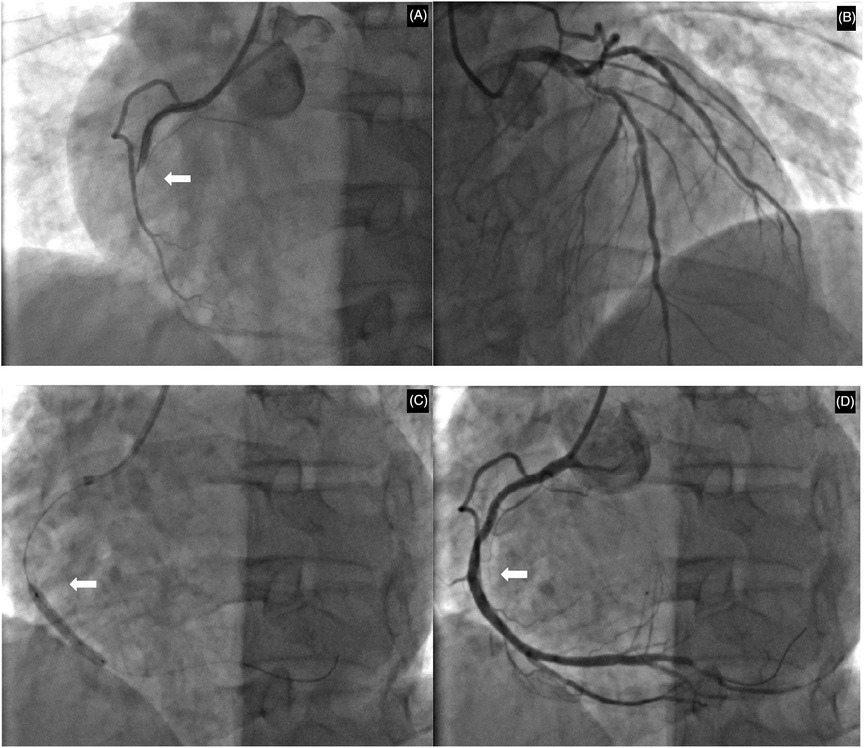

The patient's hyperthyroidism was uncontrolled due to self-discontinuation of medication. Consequently, there is an elevated risk of emergency percutaneous coronary intervention (PCI), coupled with the potential for thyroid storm. He subsequently provided informed consent and underwent the procedure. Coronary angiography findings (Figure 2): Right coronary artery: Diffuse stenosis is evident in the proximal and mid-segments, with the most severe degree reaching 60%. Complete occlusion is observed at the second bend, and distal antegrade blood flow is TIMI grade 0. Other blood vessels show atherosclerotic plaque stenosis lesions. Accordingly, a stent was implanted in the right coronary artery. Comprehensive echocardiographic assessment demonstrated: (LVEDV: 52 mm, LAS: 38 mm, RVD: 33 mm, IVSD: 10 mm, EF: 64%) Left atrial enlargement and asynchronous ventricular wall motion with mild hypokinesis of the inferior wall, accompanied by impaired left ventricular diastolic function. Thyroid ultrasound findings indicated diffuse parenchymal abnormalities and multiple nodules in the left lobe of the thyroid gland, classified as TI-RADS category 3. Postoperatively, the patient received treatment for coronary artery dilation and antiplatelet therapy including aspirin 100 mg once daily and clopidogrel 75 mg once daily. Lipid-lowering therapy included atorvastatin 20 mg combined with ezetimibe 10 mg nightly. Additional cardioprotective medications included nicorandil, sacubitril/valsartan, metoprolol succinate sustained-release tablets, and Shexiang Baoxin Pills (a Chinese herbal medicine for CAD). For hyperthyroidism management, methimazole 10 mg once daily was administered, along with multivitamin supplements and selenium yeast tablets. The patient's chest tightness resolved significantly post-procedure.

Figure 2

Coronary angiographic findings and interventional procedure. (A) Initial angiography revealing total occlusion at the second bend of the right coronary artery. (B) Angiography of the left coronary artery showing the proximal left anterior descending and circumflex arteries. (C) Balloon angioplasty being performed at the site of the occlusion. (D) Final result following successful stent deployment, with restored blood flow and resolution of the stenosis. White arrows indicate the primary lesion or intervention site.